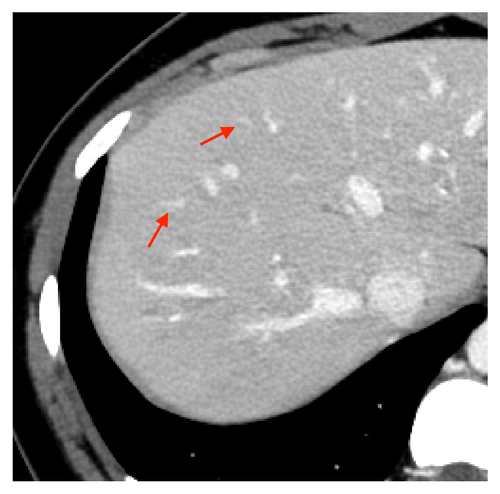

Fig. 7 and 8 show the results for two separate slices of Exam 1, a high-contrast clinical scan. Visually, results for the MSE-denoiser have smooth texture and lack detail. In contrast, BR- has more detail than MSE-denoiser, but with very nonuniform texture. The WGAN-VGG method recovers some texture and detail; however, the texture is not uniform.

From Fig. 7(7) and 8(8), TMGAN produces uniform texture, but with increased noise variance and with some details obscured by the texture. Alternatively, TMGAN-blended achieves the desired uniform texture, along with reduced noise and more visible detail. More specifically, the arrows in Fig. 7(7) indicate the detail recovered by TMGAN-blended even while maintaining the uniform target texture of TMGAN.